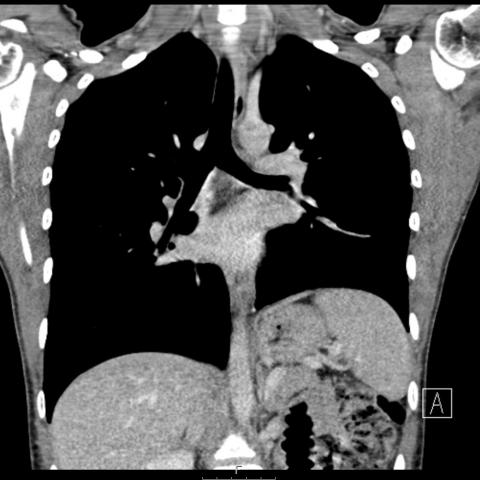

随后进行胸部对比增强CT(计算机断层扫描),结果显示非常大的团块占据左肺大部分,并且左上叶保留。团块由软组织组成,具有肉眼可见的脂肪灶,液性变薄的囊性区和多个钙化灶。CT进一步证实了纵隔移位的程度和左胸腔存在积液。纵隔淋巴结无明显肿大,无骨性病变,无肺扩张。组织学证实有大量成熟的肺内畸胎瘤。

图4冠状面CT显示,左肺内存在大量软组织团块,包括肉眼可见的脂肪、液性变薄的囊性区和多个钙化灶。少量胸腔积液,纵膈移位。